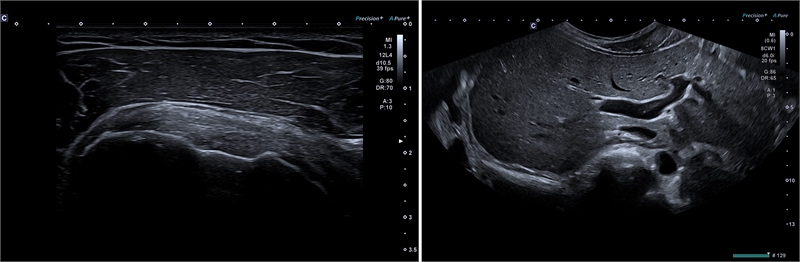

특히 이번에 처음 도입된 '프리시젼 플러스 파인 프로세싱 (Precision+ Fine Processing)' 모드는 신호를 더욱 선명하게 표현하여 이미지의 윤곽선을 뚜렷하게 만든다. 이 기능은 어플리오 비욘드에 처음 적용됐다.

▲‘프리시젼 플러스 파인 프로세싱’ 적용(왼쪽)과 ‘울트라 와이드 뷰’ 적용(오른쪽)